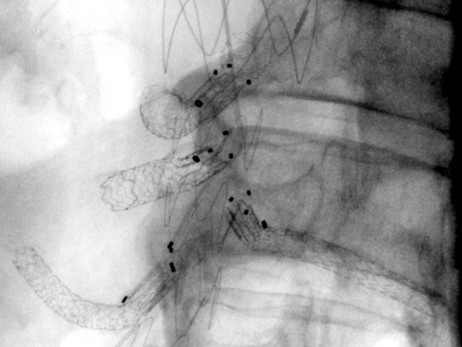

Abhängig von Ausdehnung und Lokalisation des Aneurysmas ist die endovaskuläre Therapie eine minimalinvasive, für die Patient:innen sehr schonende Behandlungsoption. Nach örtlicher Betäubung und gegebenenfalls leichten angstlösenden bzw. beruhigenden Medikamenten führen die Expert:innen der Abteilung für Radiologie und Nuklearmedizin durch die Haut eine übliche Punktion der Leistenarterie als Zugang zum Gefäßsystem durch. Anschließend wird mit Hilfe bildgebender Verfahren über ein Kathetersystem eine ummantelte Gefäßstütze (Aorten-Stentgraft) präzise innerhalb des erkrankten Gefäßabschnittes eingesetzt, um die Gefäßaussackung von innen abzudichten.

Bei einem nicht unerheblichen Anteil der Betroffenen sind keine Standard-Stentgraft-Materialien verwendbar, um eine sichere Abdichtung zu gewährleisten. In diesen Fällen kommen maßgefertigte Stentgraft-Prothesen zum Einsatz. Diese haben abhängig von der Lokalisation Verbindungen zu den übrigen wichtigen Baucharterien wie Nieren und Darm.

Ist die Gefahr eines Aortenrisses sehr hoch, beispielsweise aufgrund eines sehr großen Aneurysmas oder Schmerzsymptomatik durch das Aneurysma, kann die Fertigungszeit der individuell produzierten Aortenstentgrafts von mehreren Wochen nicht abgewartet werden. Alternativ kommen hybride endovaskuläre Techniken zu Einsatz, die Standardmaterialien miteinander kombinieren, um eine umgehende zeitnahe Versorgung durchführen zu können.

Auch eine atypische Versorgung zum Erhalt beispielsweise wichtiger zusätzlicher Nierenarterien zur Förderung der Nierenfunktion sind mit diesen Techniken umsetzbar.

Entsprechend unserem Anliegen, so viel wie möglich an vorhandenen Gefäßen zu erhalten, gelingt auch der Erhalt der Beckenarterien bei ausgedehnten aorto-iliakalen Aneurysmen mit diesen Techniken. Diese Gefäßversorgung bildet einen wichtigen Umgehungskreislauf bei arterieller Verschlusskrankheit zum Bein oder vaskulär bedingter erektiler Dysfunktion.